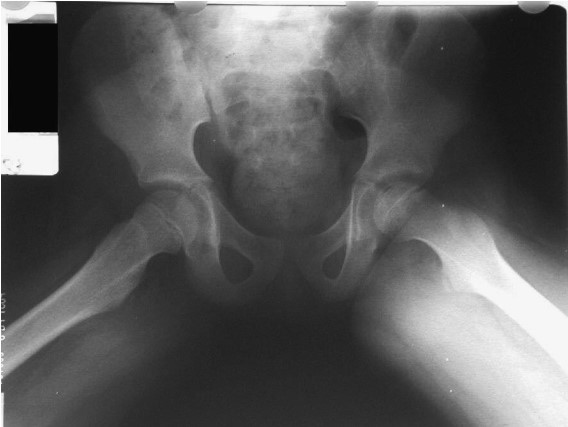

Bone anatomy:

Common bone fractures:

Joint pain differential diagnosis: